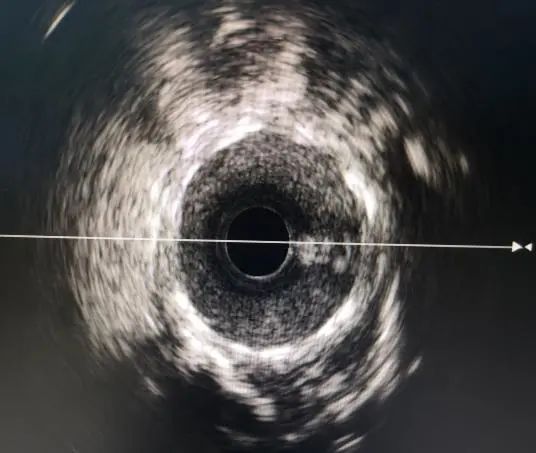

支架植入前 支架植入后

IVUS指导下可以给术者提供更准确的数值参考来进行支架植入,并对支架植入后支架的膨胀程度贴壁情况等都可以有很好的评估作用

IVUS相对于CAG是一种更加精确、更为直观的影像学补充。它更似介入医生的眼睛,帮助我们看清血管内部的结构,指导我们有效合理的运用支架,并在即时评估支架效果以及支架预后评估中都起到了不可替代作用。通过使用腔内影像对冠心病的介入治疗进行辅助指导可以更好的守护病人健康。